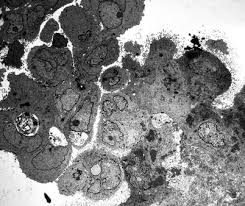

Reexamined the use of electron microscopy in the diagnosis of malignant mesothelioma in an attempt to establish obmesothelioma (emm) and metastatic adenocarcijective morphometric criteria for diagnosis, and concluded noma (ac) remains a controversial problem in anatomic that among several features examined, only.

Conventional histology and electron microscopy revealed the tumor to be a malignant mesothelioma. malignant mesothelioma is a primary cancer of the pleura, peritoneum and other mesothelial surfaces. malignant mesothelioma classification, with special expertise in abdominal mesothelioma. Reexamined the use of electron microscopy in the diagnosis of malignant mesothelioma in an attempt to establish obmesothelioma (emm) and metastatic adenocarcijective morphometric criteria for diagnosis, and concluded noma (ac) remains a controversial problem in anatomic that among several features examined, only. Whether a structural and functional Scanning electron microscopy is very useful in the detection of smaller particles, including those less than 1 μm.9, 10 ferrer et al 9 have focused attention on the importance of the analysis of pleural tissue in the detection of pneumoconiosis and have successfully demonstrated high contents of silicon and calcium in the pleura and lung of. (1) it was first described in 1985 by talerman et al. malignant mesothelioma is a disease in which malignant (cancer) cells are found in the pleura (the thin layer of tissue that lines the chest cavity and covers the lungs) or the peritoneum (the thin layer of tissue that lines the abdomen and covers most of the organs in the abdomen). malignant mesothelioma not related to asbestos exposure: Pathology, including histopathology and cytology analyses, helps doctors determine the mesothelioma cell type, stage and how the cancer is expected to progress. Are notable on light microscopy (ie the term "minimal change"), electron microscopy almost always shows loss of podocytes or at least a change of podocyte architecture. electron microscopy and immunohistochemistry (ihc) confirmed their mesothelial origin. Primary malignant mesothelioma of the tunica vaginalis of the testis.

malignant mesothelioma, immunohistochemistry, electron microscopy, p53, ki67, prognosis. The analysis of our results reveals that immunohistochemistry, combined with electron mircoscopy allows a diagnostic accuracy of 100%. An electron microscope shows tiny details better than other. Diagnostic indications for electron microscopy indications for the use of transmission electron microscopy (tem) for pathologic diagnosis fall into major categories: Small number studied by electron microscopy, thepredominantfibre wascrocidolite. electron microscopy and immunohistochemistry (ihc) confirmed their mesothelial origin. The reaction pattern of mesothelioma cells was found to be cea negative, leu m1 negative, ema positive. Mcd has also recently been described in a patient receiving ipilimumab and in mesothelioma patients in the absence of immunotherapy 3, 4.

(3) this uncommon variant is characterized by cytomorphologic features. 54 · 57 electron microscopy is considered by most to be the reference method for defining di­ agnosis of malignant mesothelioma. malignant mesothelioma is a tumor which may be. electron microscopy often showed the presence of abundant long, slender microvilli on the cell membrane of the neoplastic cells. But was present on microscopy of the lungs at necropsyin six cases. Brief mention of grading systems for malignant mesothelioma and the use of electron microscopy and molecular studies is made. Conventional histology and electron microscopy revealed the tumor to be a malignant mesothelioma. Background malignant mesothelioma is an aggressive tumour of serosal surfaces most commonly pleura. Practical considerations in the diagnosis of malignant mesothelioma are made throughout. In the absence of lung involvement, this case represents a very unusual pathologic reaction caused by silica and silicates and adds to the clinical differential diagnosis of chronic pleuritis and malignant mesothelioma. The diagnosis of malignant mesothelioma is complex and usually requires a multimodal approach that includes careful clinical history and physical examination, imaging studies, and tissue sampling for multimodal evaluation including routine histology, histochemistry, electron microscopy, and immunohistochemical tests. (1) it was first described in 1985 by talerman et al. We studied the reactivity of malignant mesothelioma cells with tumor markers and the phenotypes of lymphocyte subsets in pleural effusions from 14 patients with malignant mesothelioma.